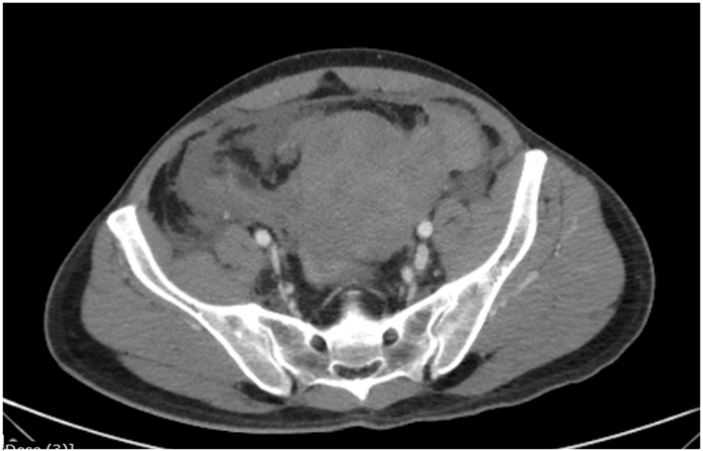

A 45-year-old gentleman, an advocate, with no prior comorbid illness, presented to emergency room of our hospital at 9pm with complaints of abdominal pain and distension, unable to void urine/defecate. On examination, he was pale, hypotensive, diaphoretic, had tachycardia and tachypnoea. Abdomen was tender and distended, predominantly lower abdomen. Rectal examination revealed a bulge over anterior rectal wall and there was no significant rectal bleed. He had undergone DGHAL RAR that morning elsewhere at 11am and his symptoms began 2 hrs after surgery. There was no history of abdominal or pelvic trauma. There was no prior history of hemorrhagic diathesis (petechiae/bleed after minor trauma/spontaneous bleeds), and coagulation studies were in normal range. Blood investigations revealed a Haemoglobin of 5gm%, which was 15 gm% in the test done before surgery the same morning. CECT abdomen revealed a large pelvic hematoma with no active contrast extravasation (Figure 1). He continued to worsen, requiring greater pressor dose, increasing abdominal distension and fall in haemoglobin. He was taken for emergency embolization of bleeder but, no contrast leak was identified (Figure 2). He was taken up for emergency laparotomy.

Figure 1: CT abdomen – pelvic hematoma and intraperitoneal blood.